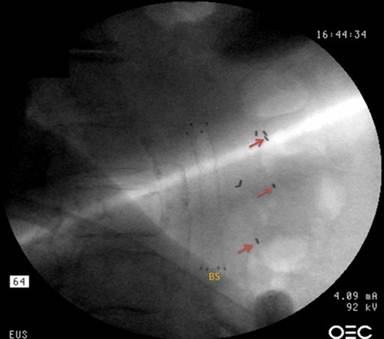

EUS is ideally suited for placement of fiducial markers in pancreatic tumors. EUS provides high quality views of the different parts of the pancreas with exceedingly accurate localization of the tumor [27]. Moreover, access to the pancreas for tissue sampling has been shown to be very safe [2]. After identification of the tumor using the linear-array echoendoscope, and after excluding the presence of intervening vasculature, EUS-guided fiducial placement is undertaken. Nineteen gauge FNA needles are best suited for this task and are usually able to accommodate fiducials up to 3 mm in length and 0.8 mm in diameter. Fiducials are preloaded into the needle by retracting the stylet and manually back-loading the fiducials into the tip of the needle. The tip of the needle is then sealed with bone wax to prevent accidental dislodgement of the fiducials. After identifying a target lesion, the tumor is punctured and the needle is appropriately positioned within the tumor. The fiducials are deployed into the tumor by simply advancing the stylet forward. To achieve best results, 4-6 fiducials should be deployed evenly around the periphery and the center of the tumor under real time EUS, and ideally, under fluoroscopic visualization as well (Figure 1).

Figure 1. EUS-guided fiducial placement in a patient with locally advanced pancreatic cancer. Several fiducials were successfully placed in the center and periphery of the tumor. A biliary stent (BS) is also seen on this fluoroscopic image. |